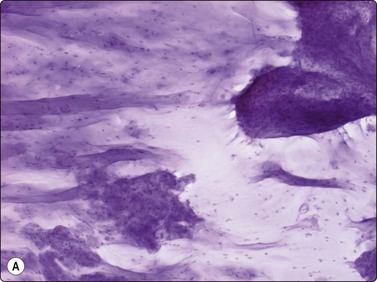

Langerhans cell histiocytosis presents as lytic and often well-defined lesions. Most cases are seen in children. The lesions may be solitary (most cases) or multiple. The long bones (femur and humerus) and the skull are the most common sites in children, and the pelvic bones and ribs in adults. The cytological pattern of Langerhans cell histiocytosis is fairly characteristic and may be diagnostic. The typical histiocytes have moderately larger and paler nuclei than those seen in common inflammatory processes. Generally reniform, the nuclei have a distinct irregular and folded outline (Fig. 16.10A). Coffee-bean nuclei has been reported to be typical of this lesion (Fig. 16.10B). The chromatin is entirely bland and nucleoli small. The cytoplasm is abundant and pale and has fairly well-defined borders. It is often vacuolated. In exceptional cases the Langerhans cells may show signs of phagocytosis. Multinucleated cells of similar type are commonly present. These can be quite large and may resemble osteoclasts in wet-fixed smears.

image image

Fig. 16.10 Langerhans cell histiocytosis (eosinophilic granuloma)

(A) Lytic bone lesion, many histiocytes with irregular reniform pale nuclei, some eosinophils (H&E, IP); (B) Coffee-bean nuclei have been reported to be typical of this lesion (H&E, HP, Oil)